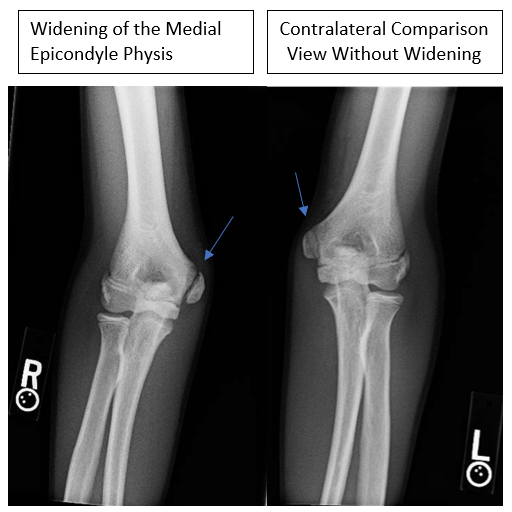

- X-rays typically demonstrate widened physis and sclerosis of the apophysis. Comparison films of the contralateral extremity can be very helpful for subtle differences

Medial Epicondyle Apophysitis

- Medial epicondyle appophysitis refers to a chronic inflammatory state where the muscles and tendons attach to the inside of the elbow

- This is an overuse injury as a result of repetitive strain across the medial elbow and associated with improper mechanics

- This typically presents with progressive medial elbow pain in overhead athletes 10 years or younger

- Pain in the late cocking and early acceleration phase is common as this is the highest valgus loads on the elbow